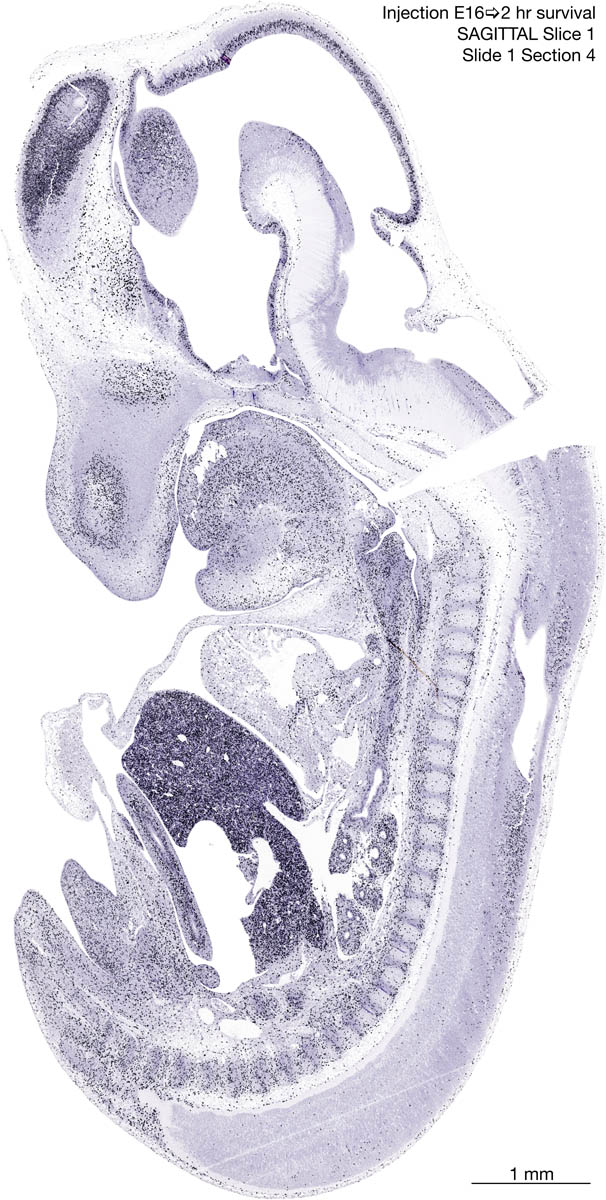

E16 2hr Survival Archived Images-Sagittal The following images are from a paraffin-embedded sagittally-sectioned E16 rat embryo exposed to tritiated thymidine 2 hours before death. Download: Large | High Res Download: Large | High Res Download: Large | High Res Download: Large | High Res Download: Large | High Res Download: Large | High Res Download: Large | High Res Download: Large | High Res Download: Large | High Res Download: Large | High Res Download: Large | High Res Download: Large | High Res Download: Large | High Res Download: Large | High Res Download: Large | High Res Download: Large | High Res Download: Large | High Res Download: Large | High Res Download: Large | High Res Download: Large | High Res Download: Large | High Res Download: Large | High Res Download: Large | High Res Download: Large | High Res Download: Large | High Res Download: Large | High Res Download: Large | High Res Download: Large | High Res Download: Large | High Res Download: Large | High Res Download: Large | High Res Download: Large | High Res Download: Large | High Res